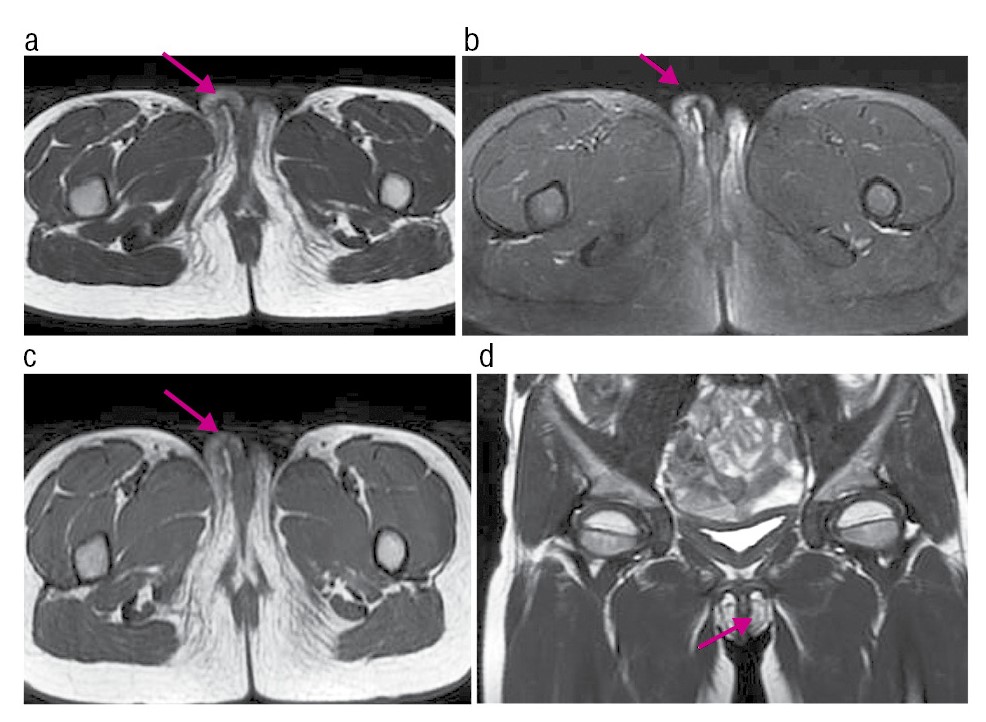

По результатам МРТ органов малого таза (январь 2024 г.): половые губы асимметричны, правая – с участками фиброзных (послеоперационных) изменений, в толще правой половой губы объемные образования, участки ограничения свободной диффузии убедительно не определяются (рис. 2).

Рис. 2. МРТ Т2-ВИ в аксиальной плоскости (а), Т2-ВИFS в аксиальной плоскости (b), Т1-ВИ в аксиальной плоскости (c), Т2-ВИ во фронтальной плоскости (d). МР-картина асимметрии половых губ с увеличением правой (указано стрелкой), с признаками наличия в толще зон фиброза.

Fig. 2. MRI T2-VI in the axial view (a), T2-VIFS in the axial view (b), T1-VI in the axial view (c), T2-VI in the frontal view (d). MR pattern of asymmetry of the labia with an enlargement in the right (indicated by the arrow), with signs of fibrosis area within the labia tissues.